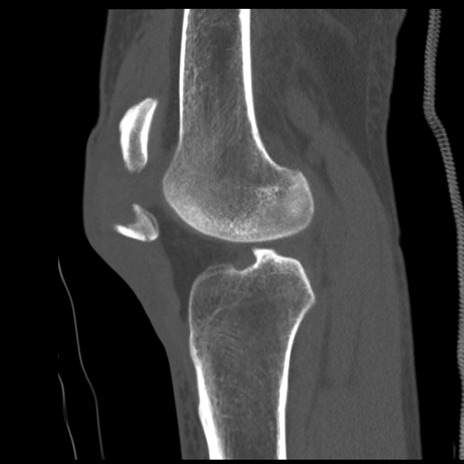

症例28 右膝関節CT(矢状断像)

異常所見と診断は?

右膝関節レントゲン

側面像